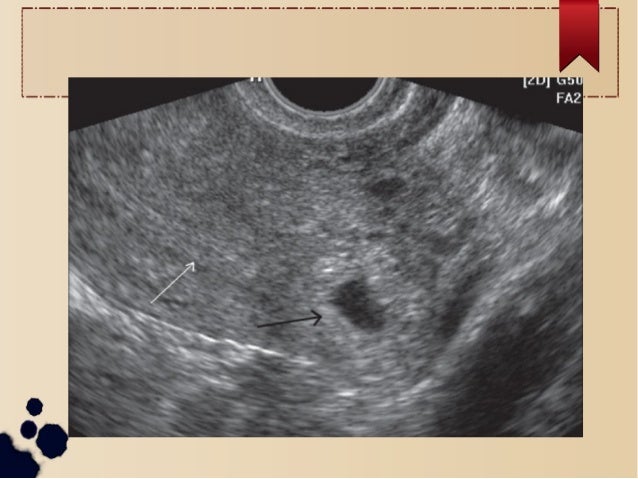

Cornual Ectopic Case Series | PPT

Cornual ectopic case series | PPT www.slideshare.net

Cornual Ectopic Case Series

Cornual ectopic case series www.slideshare.net

Ultrasonographic Appearance Of Cornual Ectopic Pregnancy. | Download

Ultrasonographic appearance of cornual ectopic pregnancy. | Download www.researchgate.net